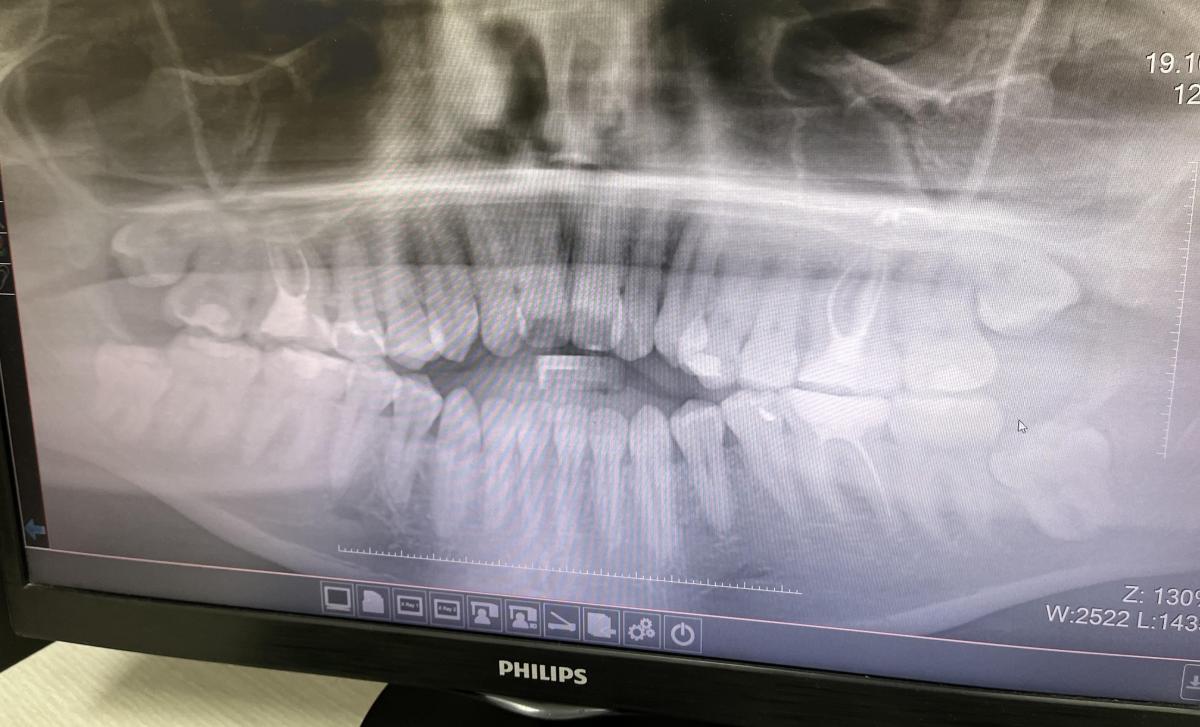

У меня открытый прикус, в детской стоматологии мне сказали делать только операцию

Сейчас уже прохожу во взрослой клинике обследование и тоже самое говорят, брекеты при открытом прикусе не помогут только члх